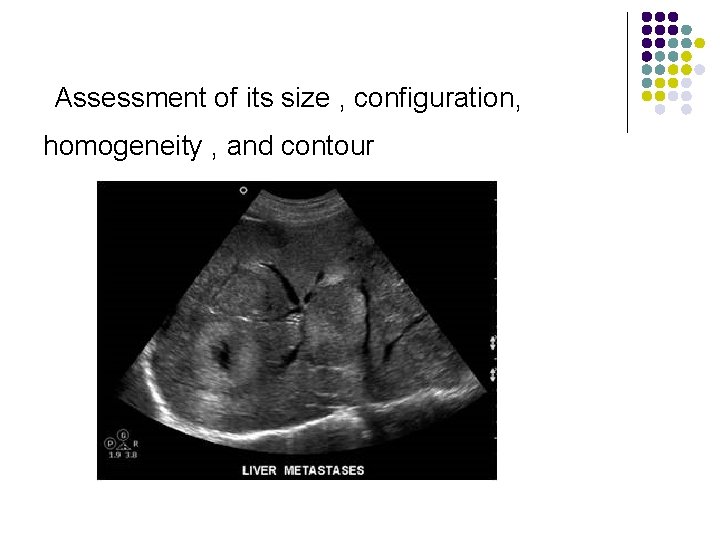

Pathology of the Live l Evaluation of the liver parenchyma includes the assessment of its size , configuration, homogeneity , and contour.

The Normal attenuation of the liver parenchyma Normal: Liver texture=homogeneous Assessment of its size , configuration, homogeneity , and contour

Abnormal Liver texture-inhomogeneous : The diffuse hepatic lesions Assessment of its size , configuration, homogeneity , and contour.

Assessment of its size , configuration, homogeneity , and contour